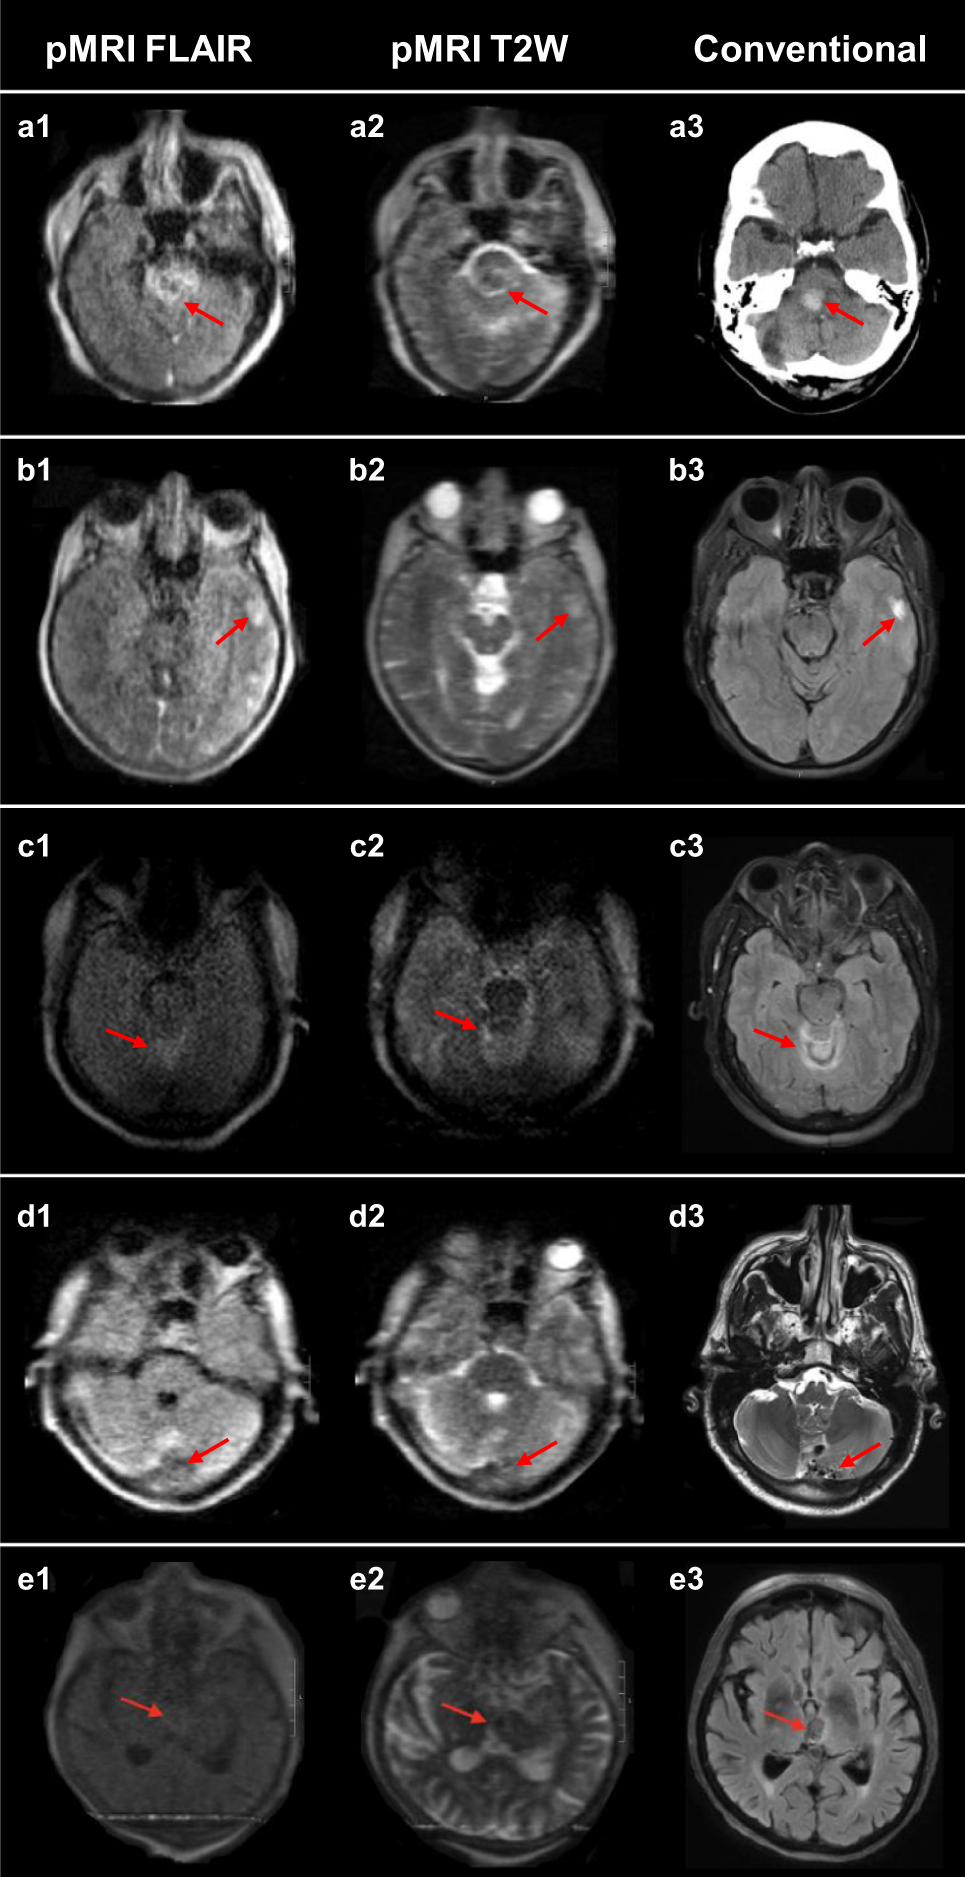

Fig. 3: False negative intracerebral hemorrhage cases.

The first and second columns are low-field FLAIR and T2W images, respectively. The third column is a gold-standard clinical examination for comparison. (3T MRI: b3, d3, and e3; CT: a3). a Right cerebellar pontine intracerebral hemorrhage (ICH). Missed by all raters. b Left temporal ICH. Missed by all raters. c Bilateral cerebellar ICH. Missed by 2/3 raters. d Left cerebellum ICH. Missed by all raters. e Left thalamus ICH. Missed by all raters.